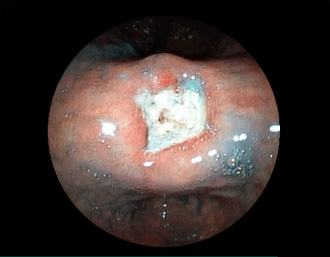

症例1:胃潰瘍(37才、男性)

①胃潰瘍(Stage A1)

健診:胃レントゲン検査で、胃角部ニッシェを指摘され当院受診。

胃角部小弯に、深くて大きな、大きさ約10mmの胃潰瘍(stage 1)

があり、潰瘍底は一部白苔はみ出しを認める。エソメプラゾールマグネシウム水和物投薬で治療開始しました。

(インジゴカルミン散布画像)